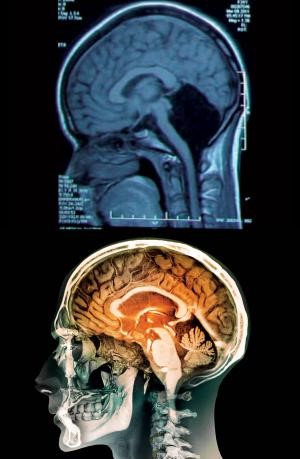

Une vue du scanner de la jeune femme (en haut) ; la tache noire montre le vide laissé par l’absence du cervelet

C’est une affaire qui met en lumière à quel point cet organe est adaptable : une jeune chinoise a atteint l'age de 24 ans sans que personne ne se rende compte qu’il lui manquait une grande partie de son cerveau !

La découverte a été faite lorsque la jeune femme a été admise à l'H?pital général de l'APL de la région militaire de Jinan dans la province du Shandong, se plaignant de vertiges et de nausées. Elle a dit aux médecins qu'elle avait eu des difficultés à marcher régulièrement pendant la plus grande partie de sa vie, et sa mère a indiqué qu'elle n'avait pas marché avant 7 ans et que son discours n’est devenu intelligible qu’à l'age de 6 ans.

Les médecins lui ont fait passer un scanner et ont immédiatement identifié la source du problème - l'ensemble de son cervelet manquait. L'espace où il devrait être était vide de tissu. Au lieu de cela, il était rempli de liquide céphalo-rachidien, qui amortit le cerveau et procure une défense contre les maladies. Le cervelet -parfois appelé le ? petit cerveau ?- est situé sous les deux hémisphères. Il est différent du reste du cerveau, car il est constitué de plis de tissu plus petits et plus compacts. Il représente environ 10% du volume total du cerveau, mais il contient 50% de ses neurones.